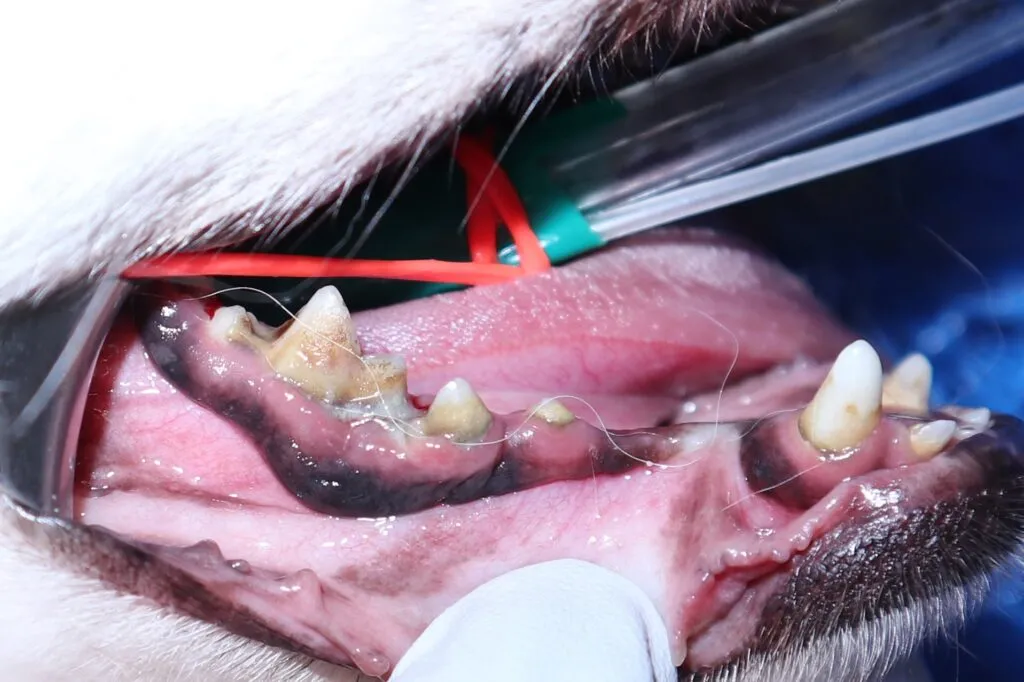

5 歳チワワ(約6 kg)の歯石除去🦷

Before

この子は、今回初めて口腔内をきれいにしました。

毎月トリミングに来ている子で、歯石が気になるとのことでした。

暗くて見えにくい歯茎の下を拡大してみることにより以前よりプラークや歯石が見つけやすくなっています。歯周病が進行している箇所は、抜歯処置も行っています。

自宅でのケアとして、 歯磨きシートで全体的に、歯ブラシで部分的に磨くように頑張ってもらっています🦷